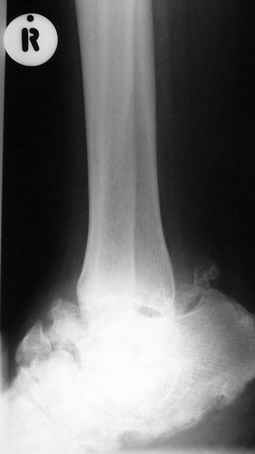

Уажаемые коллеги,представленные рентгенограмммы я показывал на нашем х-рей митинге - они были встречены с большим интересом.. Ну, ещё бы - я сам эту патологии встречал раза три за всю свою долгую жизнь:

Кто шустрый - при какой патологии встречается так называемые "суставы Шарко"?Второе приобретение доктора Эмануэла мне понравилось своим романтическим названием: Candle bone - <кость-в-виде-оплывающей-свечи> : Просто редкая патология:

VR> Кто шустрый - при какой патологии встречается так называемые <суставы Шарко>?

Сирингомиелия,

Травма спинного мозга

Опухоль

Ленар Рашитов

Т.н. нейрогенная артропатия бвает при диабете, периферических нейропатиях, заболеваниях спинного мозга... Как-то довелось вести больного с таким поражением тазобедренных суставов при третичном сифилисе.